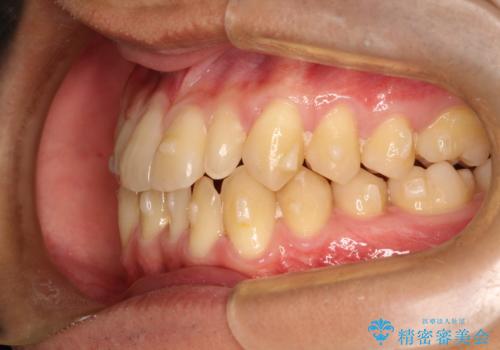

- 前歯のがたつきが気になるとのことで来院されました。

骨格的なところと、上下の歯の大きさのことを考慮して、下の前歯を1本抜歯し、インビザラインにて矯正治療することとなりました。

上の前から2番目の歯がもともと小さかったため、最後にかぶせ物を装着することで、自然な仕上がりにできました。